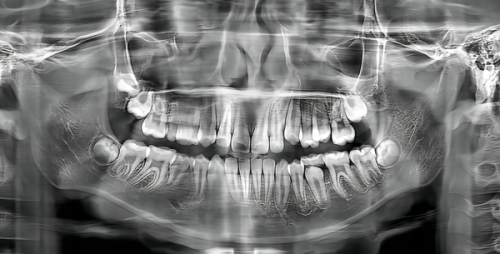

该门诊部配备了多台高端的医疗检测、治疗设备,使口腔检查诊断更科学、更全、更准。无论是口腔检查、全景片检查还是舒适超声波洁牙,都能为你提供精细的诊断和有效的治疗,让你的牙齿问题无所遁形。